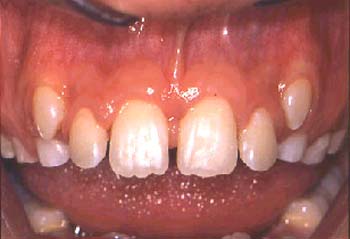

La queja principal de este paciente era la incomodidad durante el funcionamiento de los dientes anteriores inferiores. Nótese la pérdida y recesión de encía. Todos los incisivos tenían grado 2 de movilidad.

Otro factor que complicaba el caso fue que el paciente había completado dos años de tratamiento de ortodoncia para cerrar el espacio que existía en anteriores debido a la pérdida de un incisivo central por enfermedad periodontal. Hay evidencia radiográfica de pérdida de masa ósea de más del 70% en el incisivo central restante.